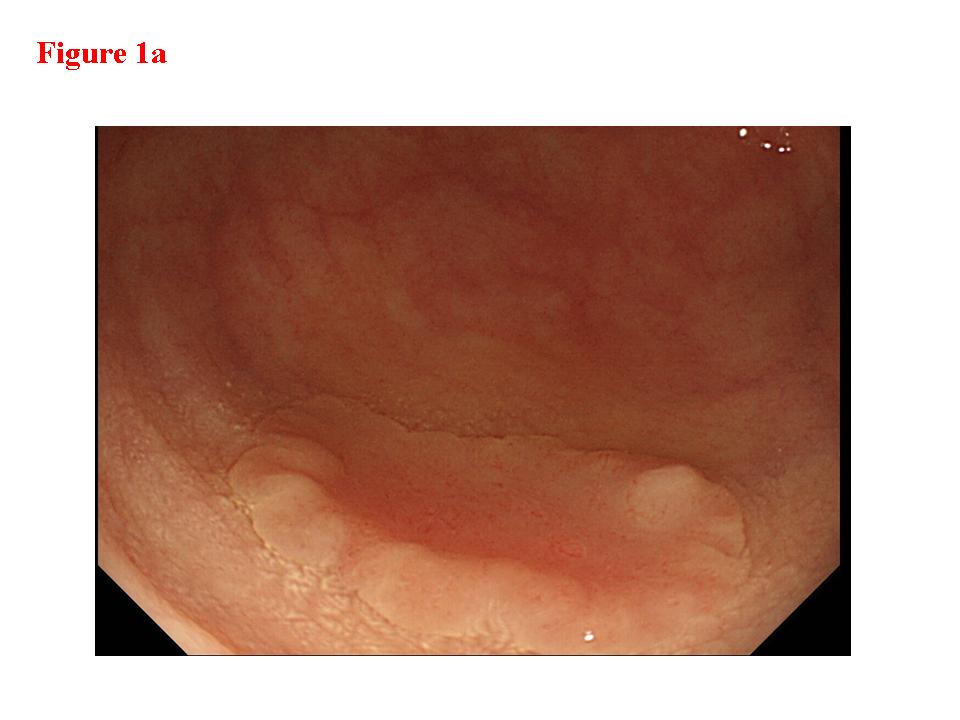

Figure 3.  Early colon cancer lesion (EUS-SM). a) Endoscopic features of superficial depressed type early colon cancer lesion.  b) The depth of the change for the third layer (submucosal layer) is more than 1 millimeter. EUS finding is EUS-SM.  Surgical operation was recommended. c) The patient once refused surgical operation and chose palliative EMR.  d) Pathological result of EMR specimen is SM deep invasion over 1 millimeter.  With this information, the patient’s mind changed and an additional surgical operation was performed.